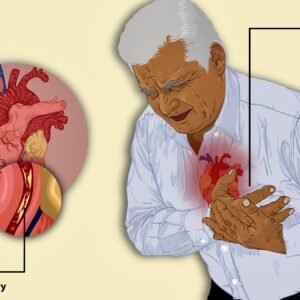

Angina

$0.00 Add to cart -